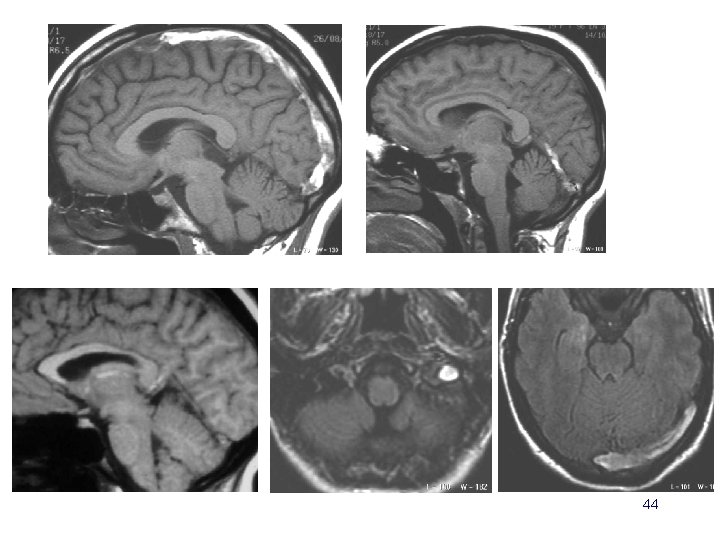

Evolution à long terme • Risque de récidive faible : 11. 7% sur 77 patients avec un suivi moyen à 6. 5 ans (Preter et al. Stroke 1996; 27: 243 -46) • Développement d ’une fistule durale – Souffle intracrânien (auscultation ++) – Diagnostic en IRM (3 DTOF) – Angiographie pré-thérapeutique • type de drainage • embolisations 83

20 ans coma d’installation rapidement progressive 84

6 mois plus tard… mais la patiente se plaint d’acouphènes. Que faut il évoquer? Que proposer? 85

86

87